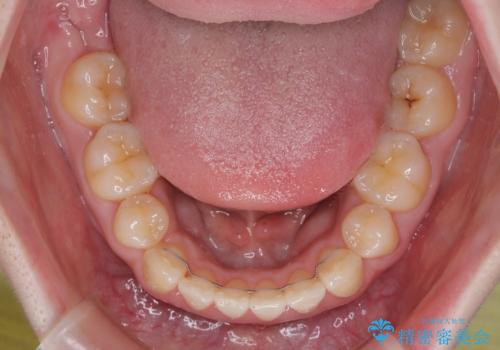

強い舌の突出癖により、上下前歯が前方に飛び出しており、特に上顎前歯は下顎よりも更に前方に位置している状態でした。

上顎前歯をしっかりと後方に移動させるため、口蓋側にアンカースクリューと補助装置を併用し、上下左右の第一小臼歯4本を抜歯し、ワイヤー装置にて矯正治療を行うこととしました。